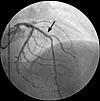

Bypasskirurgi har lavere mortalitet end koronarangioplastik efter seks år

Koronar bypasskirurgi er forbundet med en lavere mortalitet efter seks år end perkutan koronarintervention (PCI), konkluderer man i en randomiseret undersøgelse publiceret i juli i Circulation.

Forskerne bag Stent or Surgery (SoS)-studiet rekrutterede i 1996-1999 patienter med flerkarssygdomme fra 53 centre i 11 lande. De blev randomiseret til enten bypasskirurgi eller PCI med bare-metal stent.

Efter seks år var 34 (6,8%) af patienterne fra bypass-gruppen døde, mod 53 (10,9%) fra PCI-gruppen (hazard ratio 1,66). Hverken diabetesstatus eller koronarsygdomens og anginas sværhedsgrad påvirkede resultaterne signifikant.

I alt var mere end 40% af dødsfaldene ikkekardielle med en overvægt af cancerrelateret mortalitet i angioplastikgruppen (20 vs. otte tilfælde). Ifølge førsteforfatteren Jean Booth fra Royal Brompton Hospital i London kan denne ubalance påvirke konklusionens pålidelighed.

Henning Kelbæk, Hjertemedicinsk Klinik B, Rigshospitalet, kommenterer: »Der er foretaget en række randomiserede studier, som sammenligner effekten af PCI og koronar bypassoperation. SoS-studiet adskiller sig fra de øvrige dels ved en lang opfølgningstid, dels ved en usædvanlig lav mortalitet i den opererede gruppe. Individuel patientbehandling må imidlertid baseres på resultaterne fra større meta-analyser, som viser, at patienter, der PCI-behandles, oftere skal have gentaget behandlingen pga. reste-nose, men at der ikke er forskel på mortaliteten ved de to behandlingsformer. Det kan diskuteres, om operation skal foretrækkes hos patienter med diabetes og sygdom i flere koronarkar. Svaret på dette fås ved opgørelse af igangværende undersøgelser«.